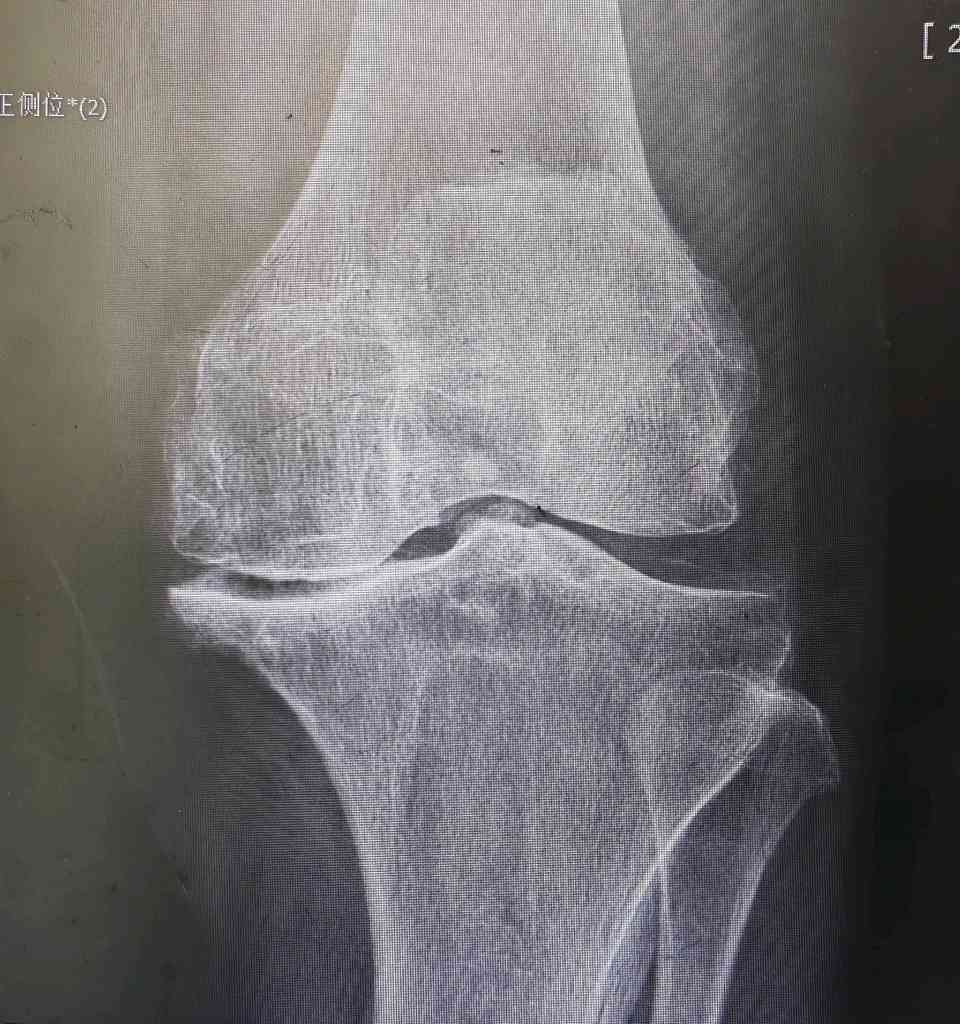

2. 对“换膝盖”的想象过于可怕: 部分老人以为手术是把整个膝盖骨都挖掉,换成一个金属疙瘩,想象起来非常恐怖。实际上,手术是精确地置换关节的磨损表面。